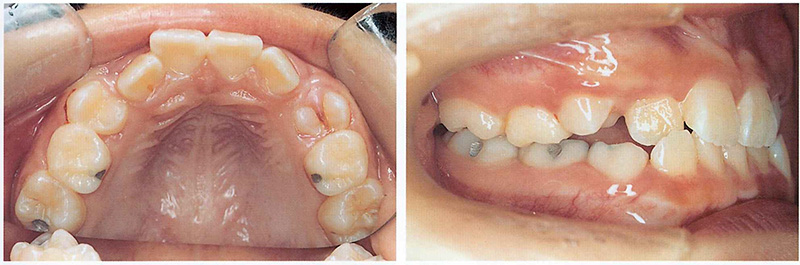

In a similar textbook case, a patient who wore a sagittal appliance had dramatic results: both impacted canines erupted naturally, and the crossbite was corrected—avoiding the need for extraction orthodontics later.